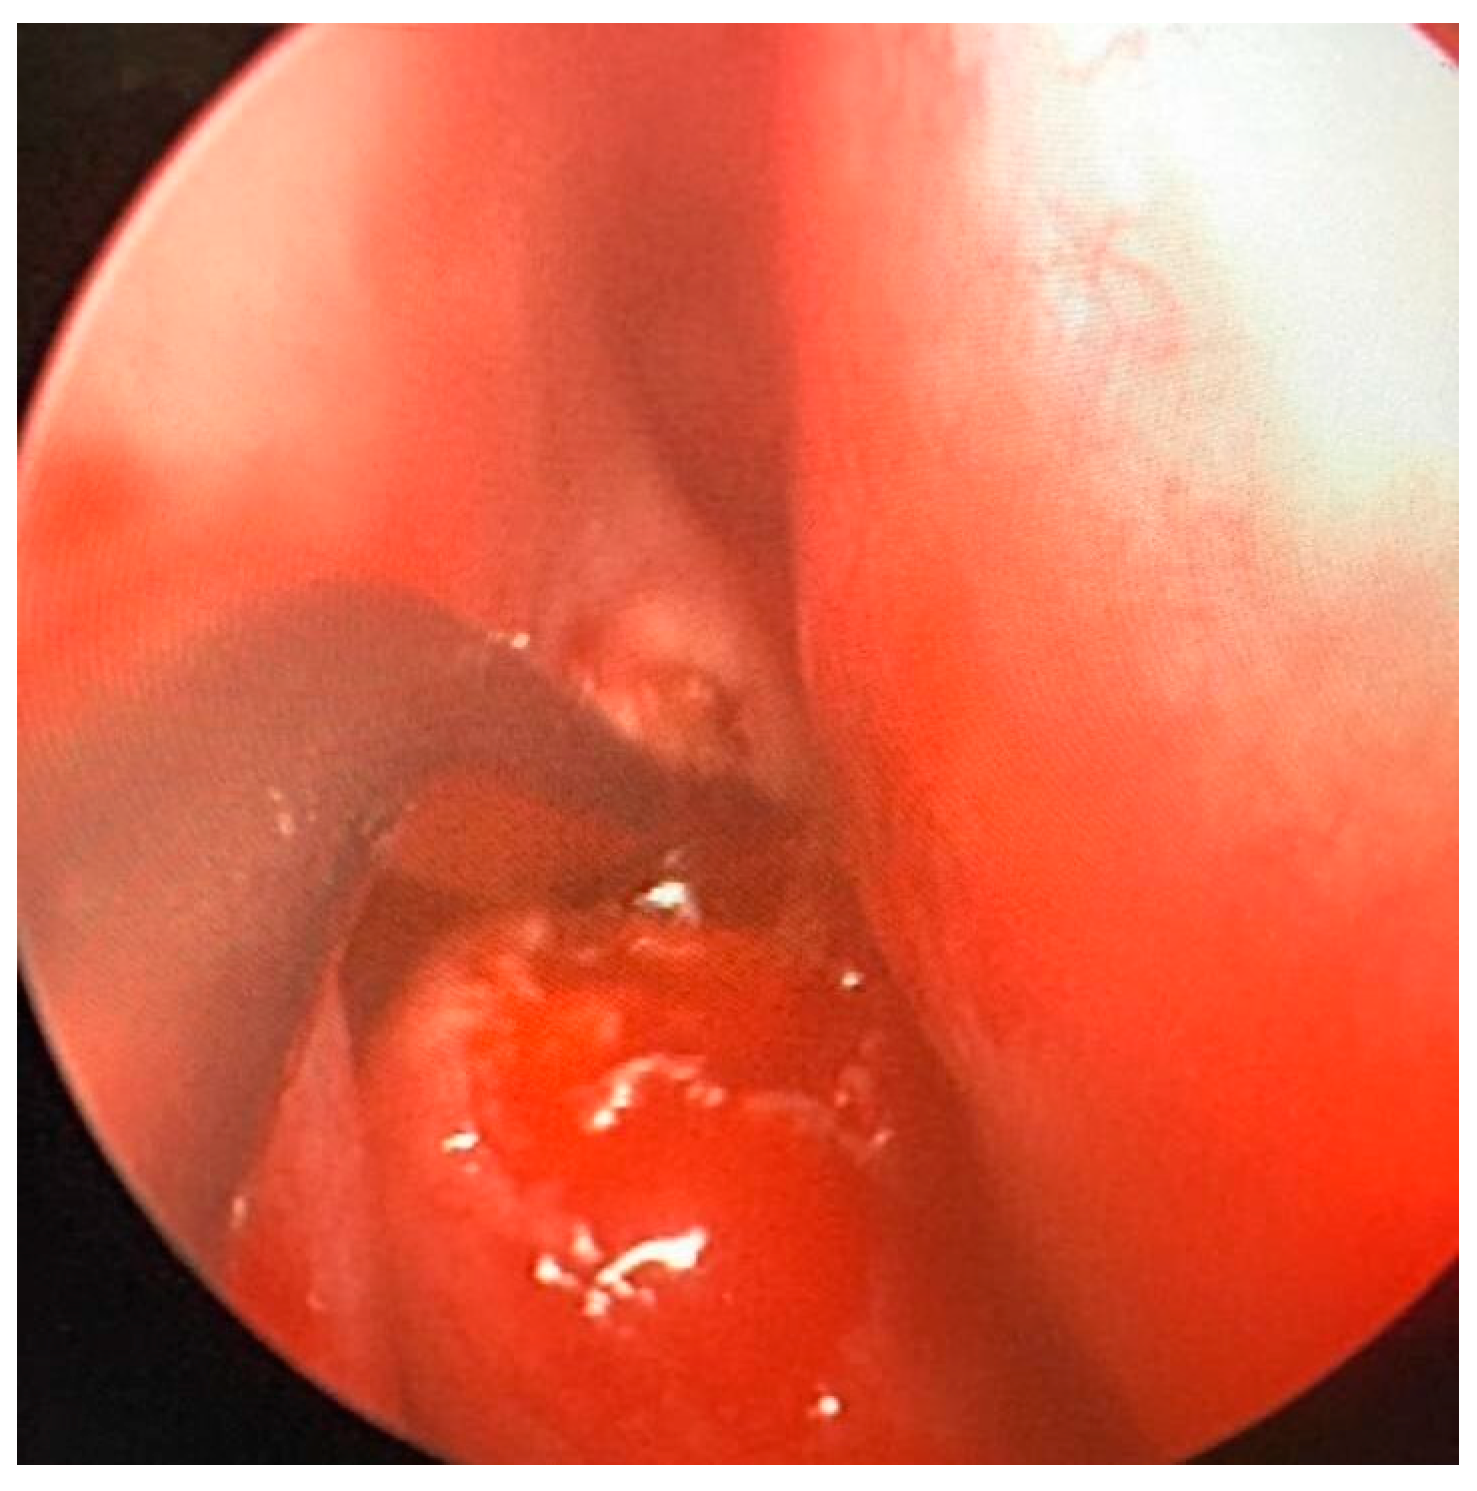

In July 2023, a 35-year-old man came to the attention of the Maxillofacial Surgery Unit of Azienda Ospedaliera Universitaria Senese of Siena to evaluate a facial asymmetry that worsened over the years. On physical examination, the eurythmy of the face was not preserved with marked exophthalmos and a dystopia of the right eye; the patient reported no sensory nerve abnormalities nor olfactory or visual deficits. The patient also reported a history of sinusitis. The skull CT scan was already performed, and it showed a large calcific-fibrotic-mixed component neoformation centered in the body of the ethmoid, extending caudally towards the right nasal fossa and cranially towards the frontal sinus occupying it bilaterally. Posteriorly, the lesion extended towards the sphenoid projecting into the anterior cranial fossa, anteriorly, and laterally towards the right orbit (Figure 4).

Figure 4. Pre-operative CT image of Patient 2. Two axial cuts are appreciated (A) The lesion localized at the ethmoidal level (B) The lesion localizedin the right frontal sinus.